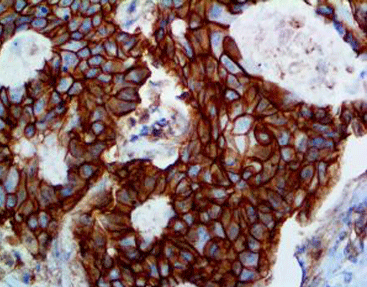

Breast cancer tissue stained with P120

The connecting family includes α-catenin, β-catenin, γ-cateninand P120 Catenin. P120 Catenin P120 Catenin is linked to E-Cadherin in the plasma next to the cell membrane to form a complex that is stable and tightly connected. A lack of E-Cadherin can lead to the accumulation of P120 Catenin in the cytoplasm. Soin lobular carcinoma of breast,a large amount of P120 Catenin in the cytoplasm is shown. However, in ductalcarcinoma of the breast, a small amount of P120Catenin is shown in membrane, not to found the accumulation in the cytoplasm. Therefore, this antibody can be used for the identification of ductal source tumors or lobular source tumors of breast.